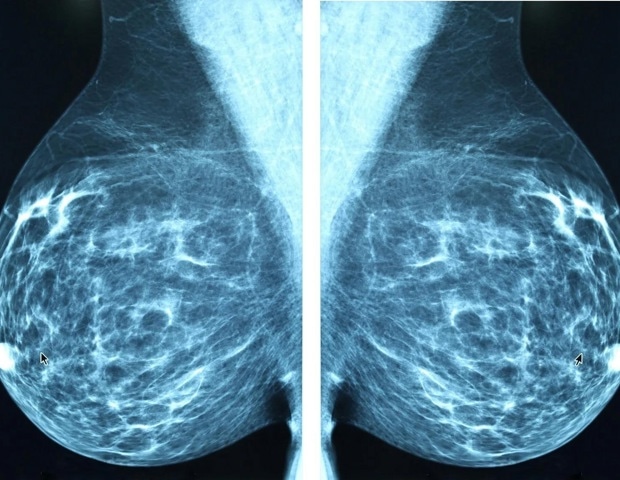

Удаление части или всей груди во время лечения рака молочной железы является потенциальным исходом для некоторых людей. Реконструктивные хирургические процедуры часто включают установку протезных имплантатов или трансплантацию тканей из других частей тела. Итак, исследователи, сообщившие в журнале ACS Applied Bio Materials, разработали прототип инъекционной пасты, полученной из клеток кожи человека, которая может помочь восстановить объем груди после удаления опухоли, с меньшим количеством рубцов и более коротким временем заживления, чем текущие варианты.

Способствуя росту кровеносных сосудов и ремоделированию тканей, сохраняя при этом низкий уровень воспаления и уменьшая капсулярную контрактуру, инъекционный бесклеточный матрикс может сделать реконструкцию груди более безопасной, менее инвазивной и более доступной, тем самым улучшая долгосрочный комфорт и косметические результаты.

Альтернативная стратегия включает в себя бесклеточный дермальный матрикс (ADM) - кожу, которая была обработана для удаления внешнего слоя. В результате остается материал с важными клеточными компонентами для заживления, включая коллаген, эластин и факторы роста. В настоящее время ADM доступен в основном в форме пластин для восстановления сухожилий или пластической хирургии, но Чиен, Чан-Йонг. Хео и его коллеги хотели создать инъекционную форму ADM, подходящую для реконструктивной хирургии молочной железы.

Исследователи взяли образец кожи, подаренный живой женщиной-участницей, и обработали его, пройдя ряд этапов, включая децеллюляризацию, замораживание и измельчение, чтобы сформировать маленькие частицы ADM. Затем они добавили воду к частицам, чтобы сформировать густую пасту. Команда ввела небольшое количество этой пасты крысам, чтобы проверить ее биосовместимость, и сравнила ее с двумя коммерчески доступными ADM. По прошествии шести месяцев у крыс не было выявлено вредных последствий для здоровья. Фактически, у животных, обработанных новой пастой ADM, вокруг введенного материала образовались более тонкие слои тканей, чем у крыс, получавших коммерчески доступный продукт. Более тонкие слои ткани предпочтительнее при процедурах имплантации груди, поскольку они с меньшей вероятностью вызывают такие осложнения, как инфекции или гематомы.